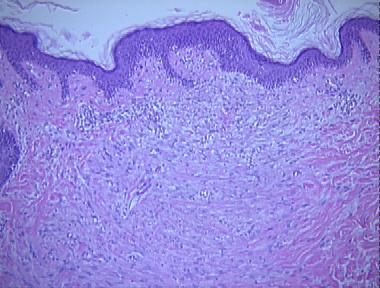

acne atrophic scar

Histologic Features